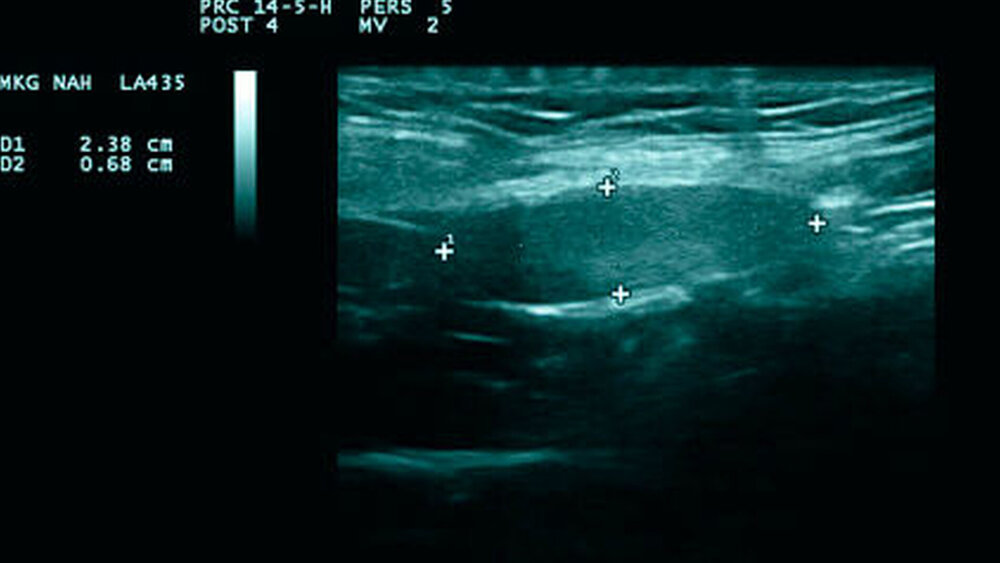

Somit stand differenzialdiagnostisch ein malignes Melanom im Raum. Vor diesem Hintergrund wurde bei sonomorphologisch einzelnen, ipsilateralen, aber zum Teil deutlich vergrößerten Lymphknoten (Abbildungen 2a und 2b) eine Sentinellymphknotenbiopsie durchgeführt, um für den potenziellen Fall des Vorliegens eines malignen Melanoms die Sicherheit für die Patientin zu erhöhen. Der Befund am Ohr selbst wurde zur Wahrung der Ästhetik als kleiner Keil entsprechend des atypischen spitzoiden Naevus entfernt (Abbildung 3).